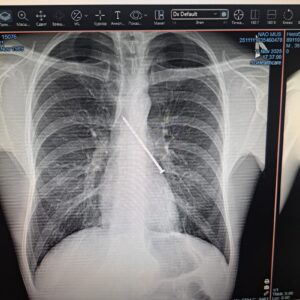

Өкпеден табылған шеге

14 қараша күні дәрігерлерді де таңғалдырған жағдай болды. Абай облыстық фтизиопульмонология орталығына жеткізілген пациенттің өкпесінен ұзындығы 10 сантиметрлік шеге табылды. Бөгде зат PENTAX FB-18V бронхоскопының көмегімен тыныс жолдары арқылы сәтті алынып, науқасқа дер кезінде көмек көрсетілді. Бұл оқиға орталық мамандарының кәсіби шеберлігін тағы бір дәлелдеді.